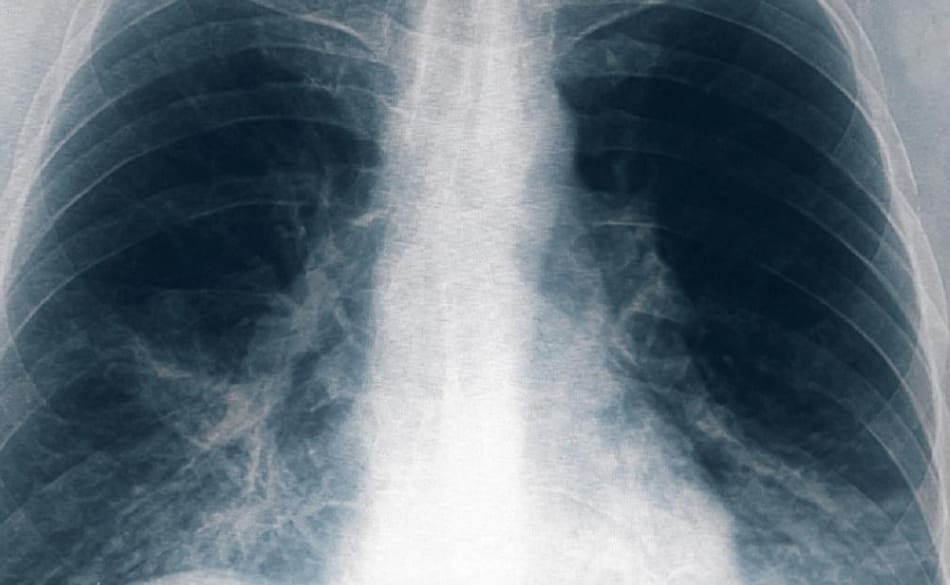

Neumonía bilateral, radiografía, Foto Télam